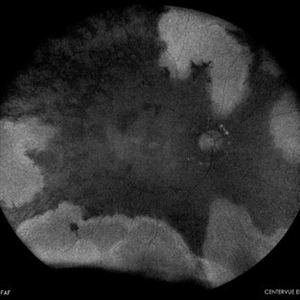

SUBHYALOID HEMORRHAGE

AUTOFLUORESCENCE IMAGE OF A 23 YEAR OLD MALE WITH SUBHYALOID HEMORRHAGE IN A CASE OF ANAEMIC RETINOPATHY

Photographer: Dr. Akansha Sharma-Retina Foundation, Ahmedabad

Condition/keywords: anaemic retinopathy, preretinal hemorrhage, subhyaloid hemorrhage